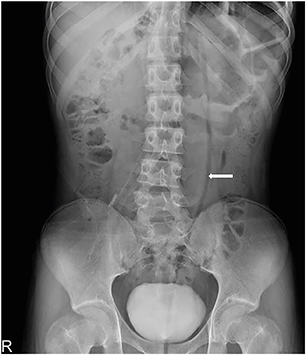

A previously healthy 16-year-old boy with stable vital signs presented with vomiting, diarrhea, distension, and abdominal pain for 4 days. On physical examination, he had abdominal distension with mild abdominal tenderness but without rebound tenderness, and a subtle metallic bowel sound. Laboratory test results were normal. An abdominal radiography revealed a dilated sigmoid colon on the left quadrant (Fig. 1). An abdominal computed tomography (CT) revealed a marked distension of the gas-filled sigmoid colon with twisting of the mesenteric vessels, confirming SV (Fig. 2). A rectal tube was inserted to decompress the volvulus (Fig. 3). He remained asymptomatic thereafter, and discharge was requested. At 2 and 7 months after his initial attack, he was readmitted to the emergency department with the same complaints. Subsequent examinations confirmed the recurrence of SV. The SV was successfully decompressed by means of a rectal tube. His parents again refused surgical treatment; however, 9 months after the first attack, he underwent laparoscopic-assisted sigmoid colectomy. We use a 12 mm port above the umbilicus, a 5 mm right upper quadrant port, a 5 mm left sided port, and a 12 mm right lower quadrant port & left lower quadrant, typically placed 2 fingerbreadths medial and 2 fingerbreadths cephalad to the anterior superior iliac spine. After mobilization of the sigmoid colon, the colon was transected at the rectosigmoid junction with an endolinear stapler (SigniaTM Stapling System; Medtronic, Minneapolis, MN, USA). The umbilical incision was extended. The divided sigmoid colon was exteriorized, and the redundant part was resected. A sigmoid colon section of 34 cm was resected; end-to-end colorectal anastomosis was performed intracorporeally using a circular stapler (ECHELON CIRCULARTM 25 mm Powered Stapler; Ethicon, Bridgewater, NJ, USA). A seromuscular biopsy specimen from the distal colon submitted for histopathologic examination showed normal ganglion cells. On postoperative day 3, he was started on water intake; subsequently, eating progressed successfully. He was discharged without complications on postoperative day 10.

Fig. 2

Coronal abdominal computed tomography showing a dilated sigmoid colon with whirl pattern (arrow) of the mesentery.